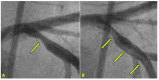

Background: In the study of coronary artery disease, the mechanisms underlying atherosclerosis initiation and progression or regression remain incompletely understood. Our research conceptualized the cardiovascular system as an integrated network of pumps and pipes, advocating for a paradigm shift from static imaging of coronary stenosis to dynamic assessments of coronary flow. Further review of fluid mechanics highlighted the water hammer phenomenon as a compelling analog for processes in coronary arteries. Methods: In this review, the analytical methodology employed a comprehensive, multifaceted approach that incorporated a review of fluid mechanics principles, in vitro acoustic experimentation, frame-by-frame visual angiographic assessments of in vivo coronary flow, and an artificial intelligence (AI) protocol designed to analyze the water hammer phenomenon within an acoustic framework. In the analysis of coronary flow, the angiograms were selected from patients with unstable angina if they had previously undergone one or more coronary angiograms, allowing for a longitudinal comparison of dynamic flow and phenomena. Results: The acoustic investigations pinpointed pockets of contrast concentrations, which might correspond to compression and rarefaction zones. Compression antinodes were correlated to severe stenosis, due to rapid shifts from low-pressure diastolic flow to high-pressure systolic surges, resulting in intimal injury. Rarefaction antinodes were correlated with milder lesions, due to de-escalating transitions from high systolic pressure to lower diastolic pressure. The areas of nodes remained without lesions. Based on the locations of antinodes and nodes, a coronary acoustic action map was constructed, enabling the identification of existing lesions, forecasting the progression of current lesions, and predicting the development of future lesions. Conclusions: The results suggested that intimal injury was likely induced by acoustic retrograde pressure waves from the water hammer phenomenon and developed new lesions at specifically exact locations.